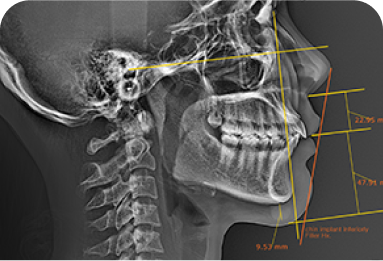

수술 전 3D-CT를 통해 신경의 위치를

1mm까지 분석하고,

원장님이 직접 수술 경로를 디자인하여

신경 손상을 원천 차단합니다

* 수술전 원장님이 직접 디자인한 사진입니다